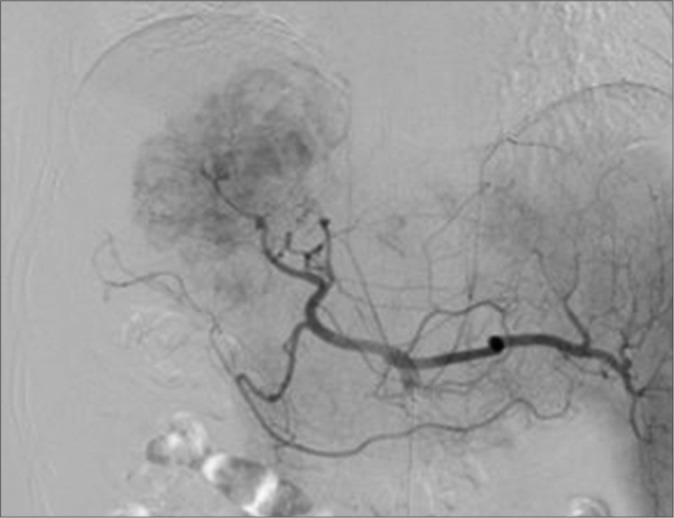

We present a case involving a 60-year-old male with multifocal hepatocellular carcinoma (HCC), emphasizing the critical need for vigilant post-procedural monitoring following the interruption of drug-eluting beads transarterial chemoembolization (DEB-TACE) due to an allergic reaction. The patient, who had a history of various treatments for HCC, underwent DEB-TACE. During the procedure, he experienced an anaphylactic shock, presumably due to an allergy to the treatment components (iodinated contrast agent), resulting in the procedure's discontinuation. Initially stable, the patient was later found to have intra-abdominal bleeding, a complication associated with the vascular lake phenomenon (VLP), detected on post-procedural imaging. Re-embolization using gelatin particles was performed to address the VLP. It remains unclear whether the shock experienced during the DEB-TACE procedure was due to the allergic reaction or the rupture of the VLP. This case underscores the complexities in managing DEB-TACE, the necessity of careful monitoring for VLP, and the challenges in diagnosing and managing allergic reactions during such procedures. In conclusion, it is crucial to consider that VLP can occur at any time during or after DEB-TACE. Assessing the presence of VLP using digital subtraction angiography before the termination of the procedure is essential. However, when an allergy to the iodinated contrast agent is suspected, as in this case, careful follow-up with abdominal ultrasound and computed tomography might be necessary to assess the presence of intra-abdominal hemorrhage associated with VLP.

我们介绍了一例 60 岁男性多灶性肝细胞癌(HCC)患者的病例,强调了因过敏反应而中断药物洗脱珠经动脉化疗栓塞术(DEB-TACE)后进行术后监测的重要性。患者曾接受过多种 HCC 治疗,接受了 DEB-TACE。在手术过程中,他出现了过敏性休克,可能是由于对治疗成分(碘造影剂)过敏,导致手术中止。患者最初病情稳定,但后来发现腹腔内出血,这是一种与血管湖现象(VLP)有关的并发症,在手术后的成像中被发现。为解决 VLP 问题,使用明胶颗粒进行了再次栓塞。目前还不清楚 DEB-TACE 过程中出现的休克是由于过敏反应还是 VLP 破裂所致。该病例突出说明了 DEB-TACE 管理的复杂性、仔细监测 VLP 的必要性以及在此类手术中诊断和管理过敏反应的挑战性。总之,必须考虑到在 DEB-TACE 期间或之后的任何时候都可能出现 VLP。在手术终止前使用数字减影血管造影术评估是否存在 VLP 至关重要。不过,如果怀疑患者对碘化造影剂过敏,就像本病例一样,可能需要通过腹部超声波和计算机断层扫描进行仔细随访,以评估是否存在与 VLP 相关的腹腔内出血。